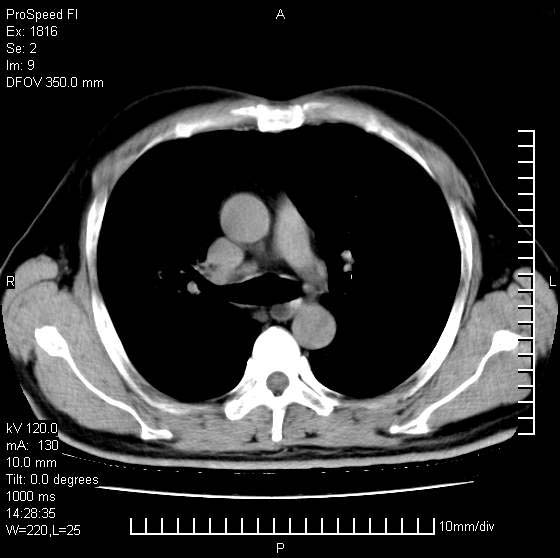

洞壁较厚内壁比较光整,两个病灶有关联性,纵隔淋巴结不大,考虑结核性空洞。

壁较厚内壁比较光整,两个病灶有关联性,纵隔淋巴结不大,考虑结核性空洞